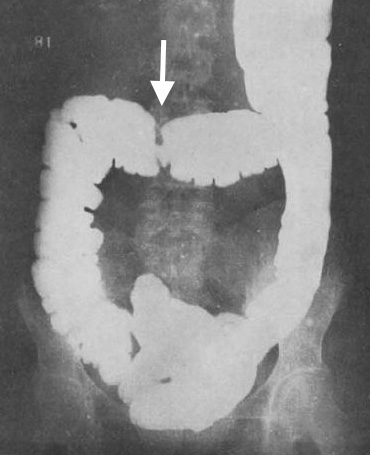

同じく1923年,Fischerは結腸を充盈したバリウムの排出後に肛門から透視下に空気を注入する二重造影法を開発し,その有用性を報告した[→原著論文].Fischer法は,濃度20~40%の薄いバリウムを大量に使用するもので,充盈法に比べれば粘膜面の情報は格段に増えたが,小さなポリープのような微細な病変の描出にはまだ不十分であった.1950年,アメリカのGianturcoは,薄いバリウムを充盈して,120~130kVの高圧撮影を行なうことにより隆起性病変の透亮像を描出する方法を考案したが,やはり小病変の診断は難しかった[12].1955年にスウェーデンのWelinは,70~100%の高濃度バリウムを比較的少量使用する方法を開発し[→原著論文],ようやく詳細な粘膜像が得られるようになった.1967年にはこの方法による36,000例の経験を報告し[13],60年代,70年代の米国ではこのWelin法を基本とする撮影法が普及した.1979年,Lauferの教科書[7]で上部消化管造影とあわせて技術的にほぼ完成をみた.

しかし注腸造影の進歩の背景には,前処置法の改良があったことを忘れてはならない.Fischer法,Welin法はいずれも前処置として強力な下剤,浣腸による洗腸が必要であったが,これは術者にとっても患者にとっても大きな負担で,自ずから適応も限られることになった.1961年,アメリカのBrownは洗腸を廃し,低残渣食と下剤を使用する新しい前処置法,いわゆるBrown法を発表した.これは患者の負担が少なく,効果も確実であることから急速に普及した[→関連文献].

充盈・圧迫法(single contrast法)と二重造影法の優劣については長く議論された.二重造影法は粘膜面の描出についてはもちろん有利であるが,全結腸を一望の下に観察できず,症例毎に腸管の走向に応じた個別の検査技術が要求される点が欧米では敬遠された.このためもあって1980年以降,大腸内視鏡の普及とともに欧米では注腸造影は徐々に衰退した[14].伝統的に二重造影法の技術に優れた日本では事情が異なり,長年にわたって大腸内視鏡と共存して来たが,近年はCT colonographyの発展もあってほとんど行なわれなくなっている.